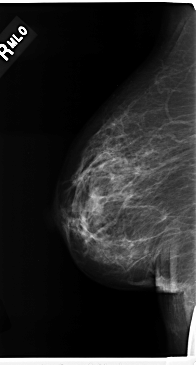

C_0206_1.RIGHT_MLO

RIGHT_MLO LINES 4736 PIXELS_PER_LINE 2536 BITS_PER_PIXEL 12 RESOLUTION 50 NON_OVERLAY